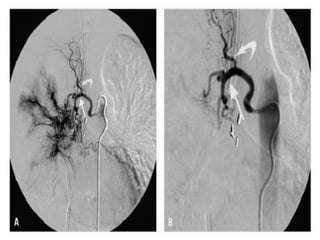

Bronchial artery embolization